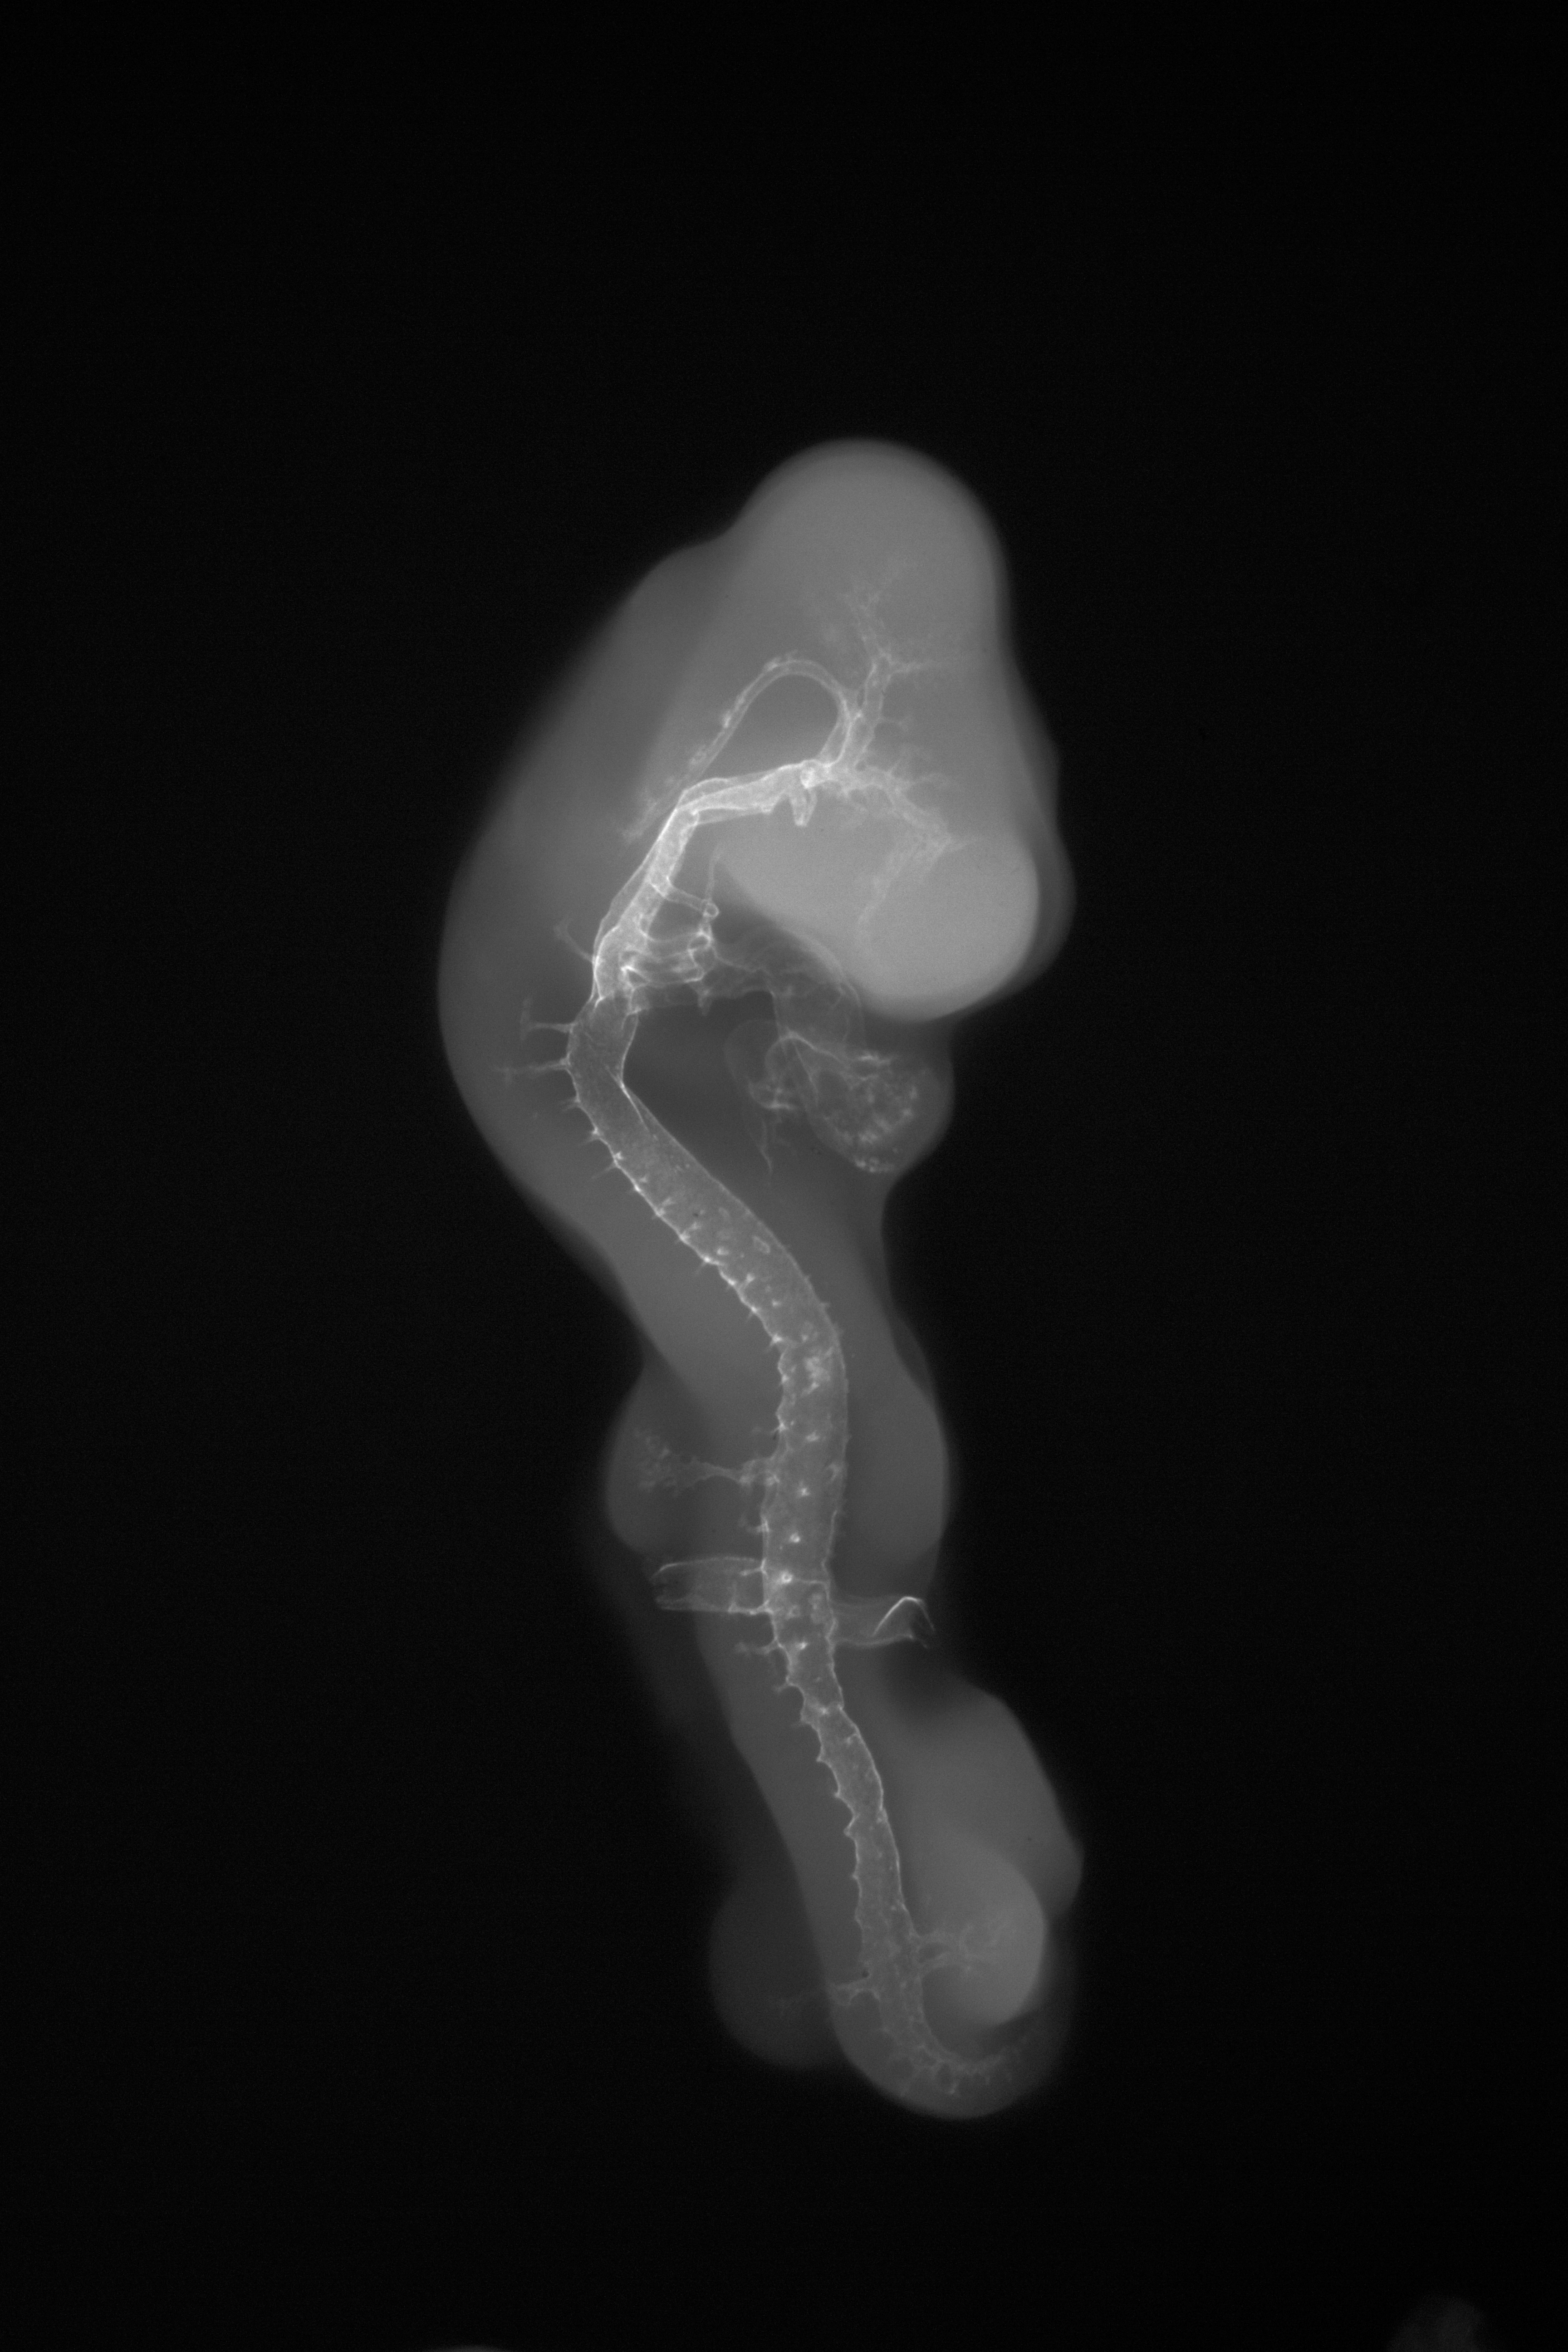

Chick Embryo Microangiography

Hamburger-Hamilton (HH) Stage 22 (approx. 4 days)

X-Ray Micrographs